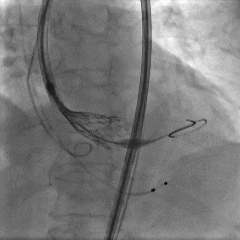

术中影像

左冠造影

左冠狭窄处行PCI处理

PCI后左冠造影,血流通畅

右冠造影

右冠狭窄处行PCI处理

PCI后右冠造影,血流通畅